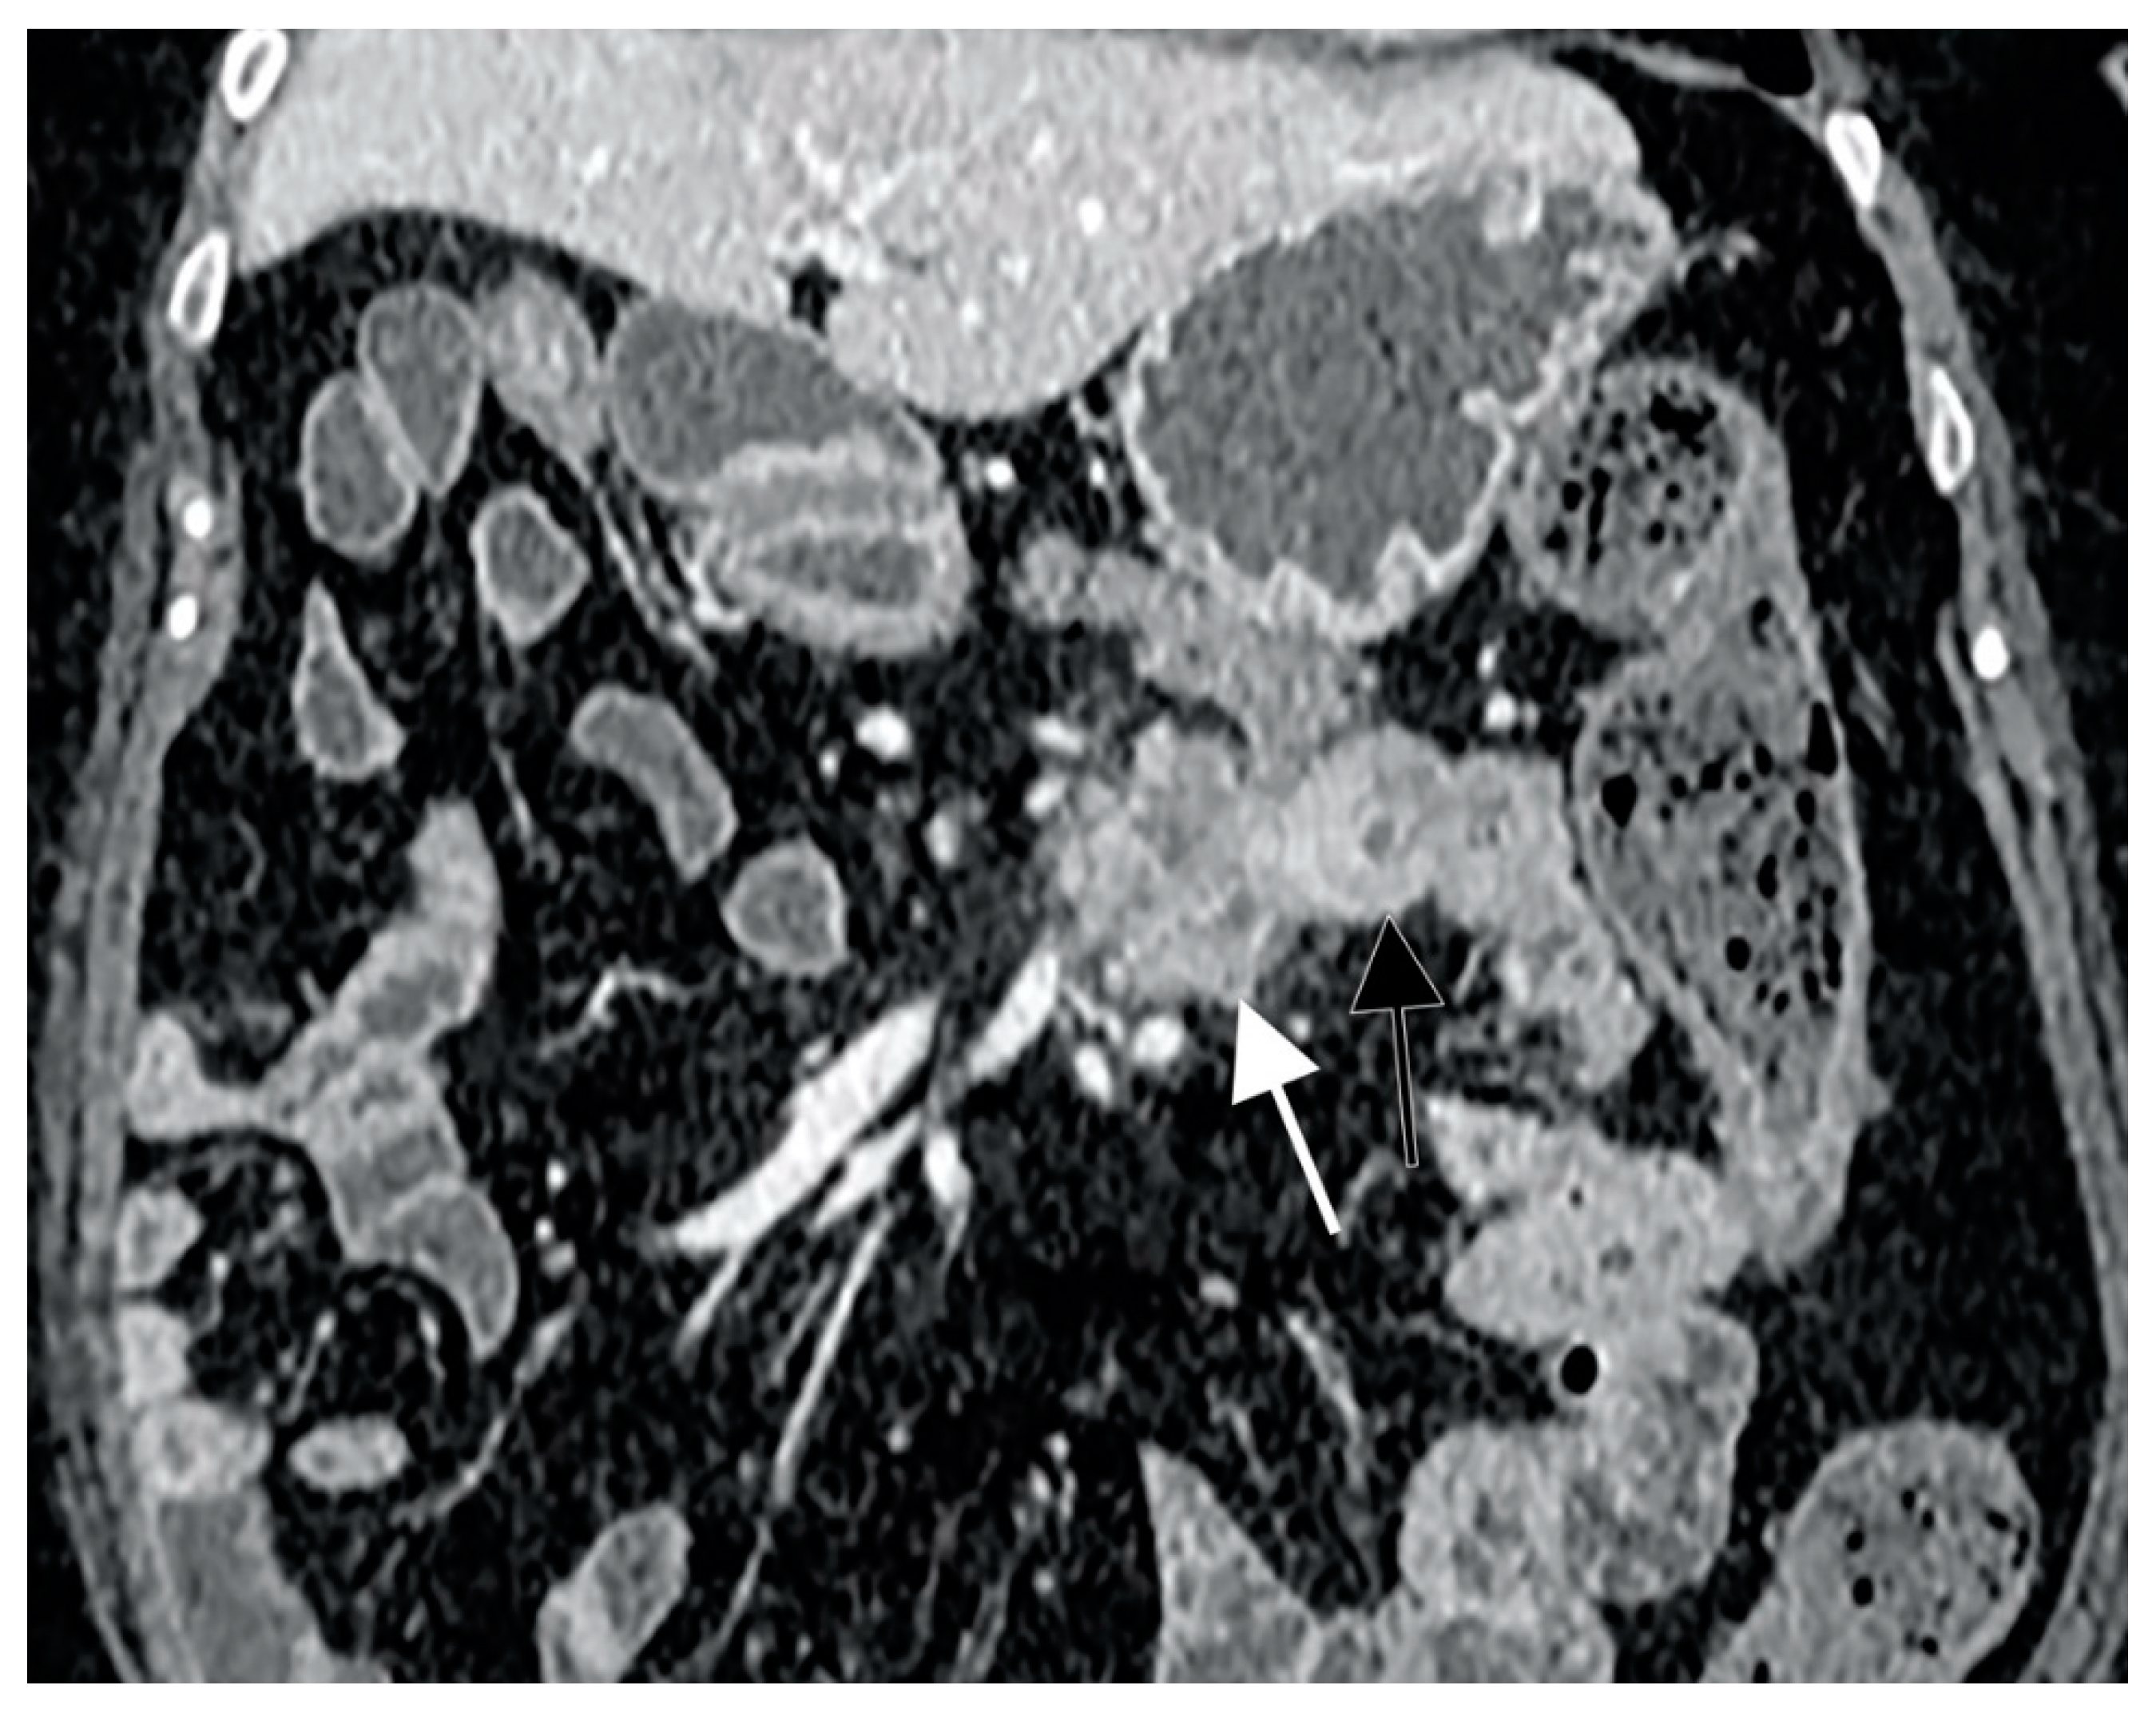

- Minordi, L.M.; Binda, C.; Scaldaferri, F.; Holleran, G.; LaRosa, L.; Belmonte, G.; Gasbarrini, A.; Colosimo, C.; Manfredi, R. Primary neoplasms of the small bowel at CT: A pictorial essay for the clinician. Eur. Rev. Med. Pharmacol. Sci. 2018, 22, 598–608. [Google Scholar] [PubMed]